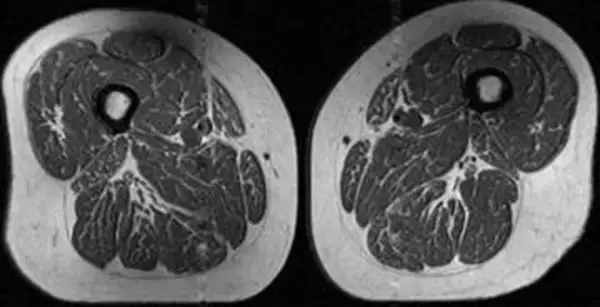

(CNN) 見事な霜降りの入った高級肉のように見える画像は、きめ細かく柔らかなステーキを思わせる。し...